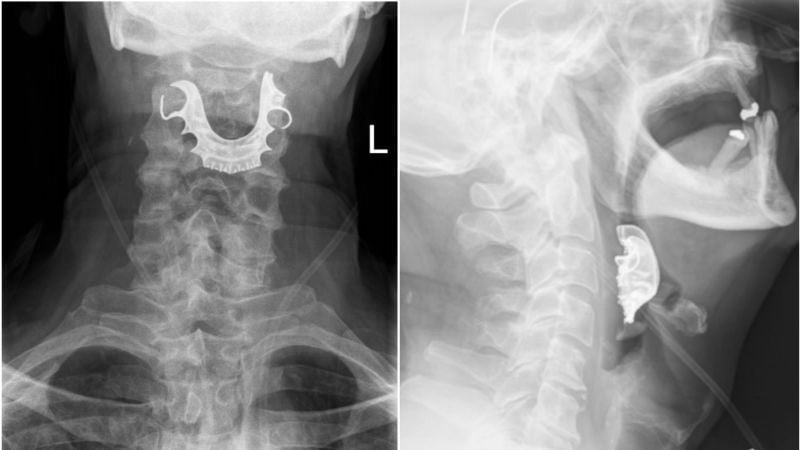

Ésta es una historia que te hará tener pesadillas cuando seas mayor. Los médicos dicen que este anciano pasó por un terrible calvario porque sus cirujanos se habían olvidado de quitarle la dentadura postiza, que quedó alojada en su garganta durante una operación. Según uno de los médicos británicos que atendieron a este hombre de…